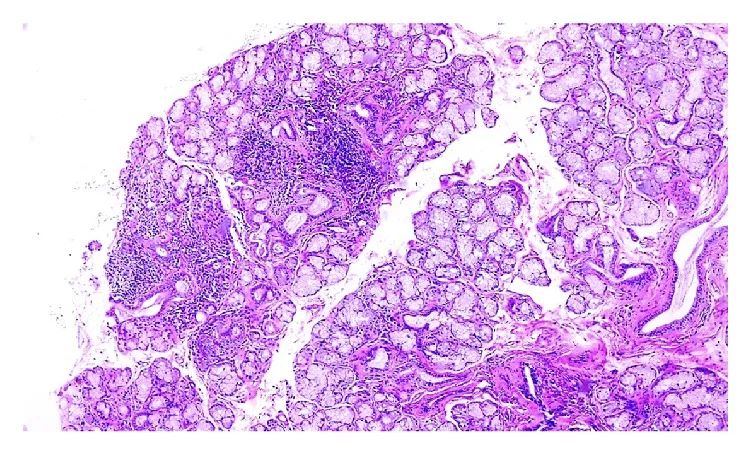

入院时的生命体征:体温36.3℃,心率每分钟54次,呼吸频率每分钟20次,室温下血氧饱和度97%,毛细血管血糖103g/dL,血压100/60mm/Hg。体格检查发现深部肌腱反射整体减弱,近端和远端肌力Lovett评分为3/5,舌干。实验室试验见表1。小涎腺活检如图1所示。根据所有的实验室结果,诊断为pSS的远端肾小管酸中毒(RTA)。先静脉注射氯化钾和碳酸氢钠治疗低钾血症和代谢性酸中毒,然后予以羟氯喹治疗。患者出院后,在接下来的8个月里,每两个月随访1次。

图1小涎腺活检的全景照片。观察到慢性淋巴细胞局灶性涎腺炎。